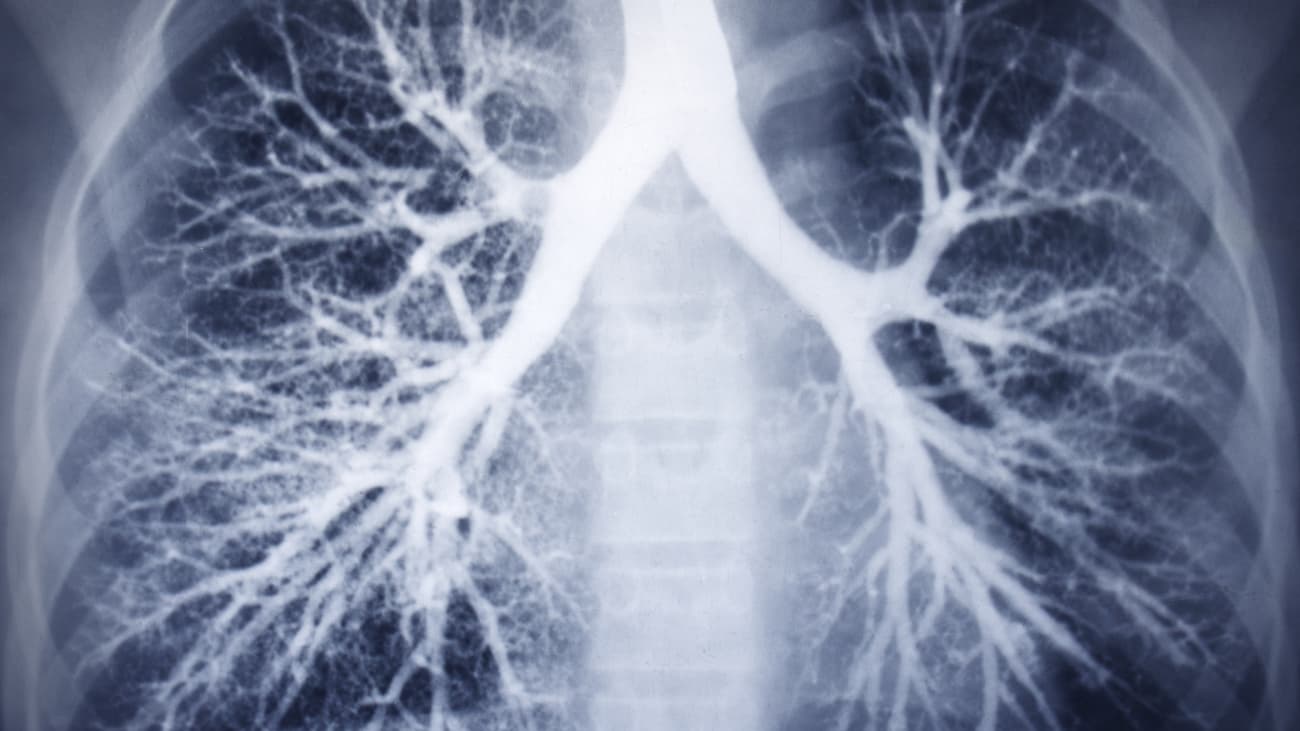

[MUSIC PLAYING] SPEAKER 1: Lung cancer may have finally met its match. Over the years lung cancer has had historically poor survival rates. Mostly because, by the time we found lung cancer in patients, it was often times either locally advanced, or metastatic. Over the years, we have tried sputum Scientology's, chest X-rays, all of which have failed to catch lung cancer early enough to make a difference in most patients. Fortunately, lung cancer screening has now been officially adopted by the United States Preventative Task Force meeting, and therefore covered by Medicare, in the form of low dose non-contrast CT scans of the chest. When we think about the reasons that breast cancer, colon cancer, prostate cancer have such great survival rates, and cure rates, is because we can catch them early, before the patients have symptoms. By using a non-conscious CT scan of the chest, we can now find nodules small enough that, when we do identify them we can offer early stage curative treatments which, oftentimes, include a combination of surgery, radiation therapy or chemotherapy. John Muir Health is very excited to be an active participant in this program. It will allow our Medicare patients, and our commercial patients, to identify their lung cancers early. As a Thoracic surgeon, I'm very excited that lung cancer has finally met its match. By identifying these cases in the very earliest stage, will be able to cure patients at the same rate that breast cancer, colon cancer and prostate cancer have. Thank you for watching. [MUSIC PLAYING]